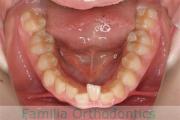

- ≫治療前

上顎

下顎

- ≫治療後